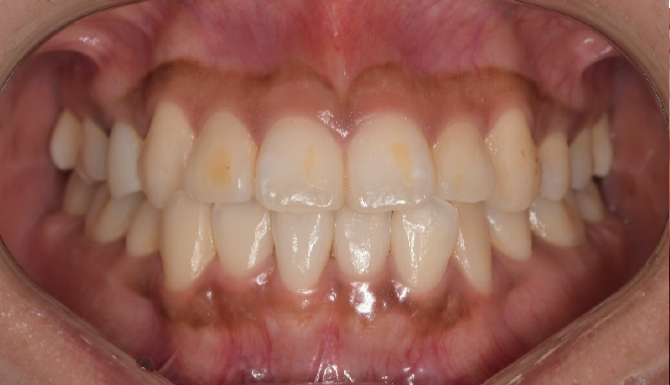

CASE1

Before

After

年齢・

性別

20代・女性

主訴 歯ぐきの色が気になる

治療

回数

1回

費用

ガムピーリング 上下顎

11,000円×1

(2025年9月現在)

内容

ガムピーリング

リスク・

副作用

・ヒリヒリとした痛み

・フェノール、アルコール類にアレルギーは禁忌

・施術後1〜3日くらいは歯ぐきが白っぽくなる